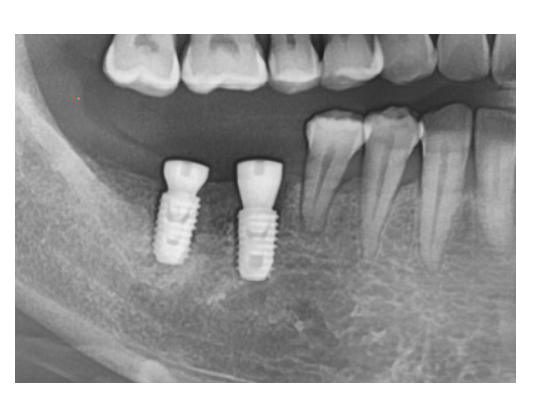

뼈가 군데 군데 부족하여도

수술은 가능합니다!

다만 예후에 영향을 끼칠 수 있는데요.

위의 사진속 뼈 음영 색깔이 다른게 느껴지시나요?